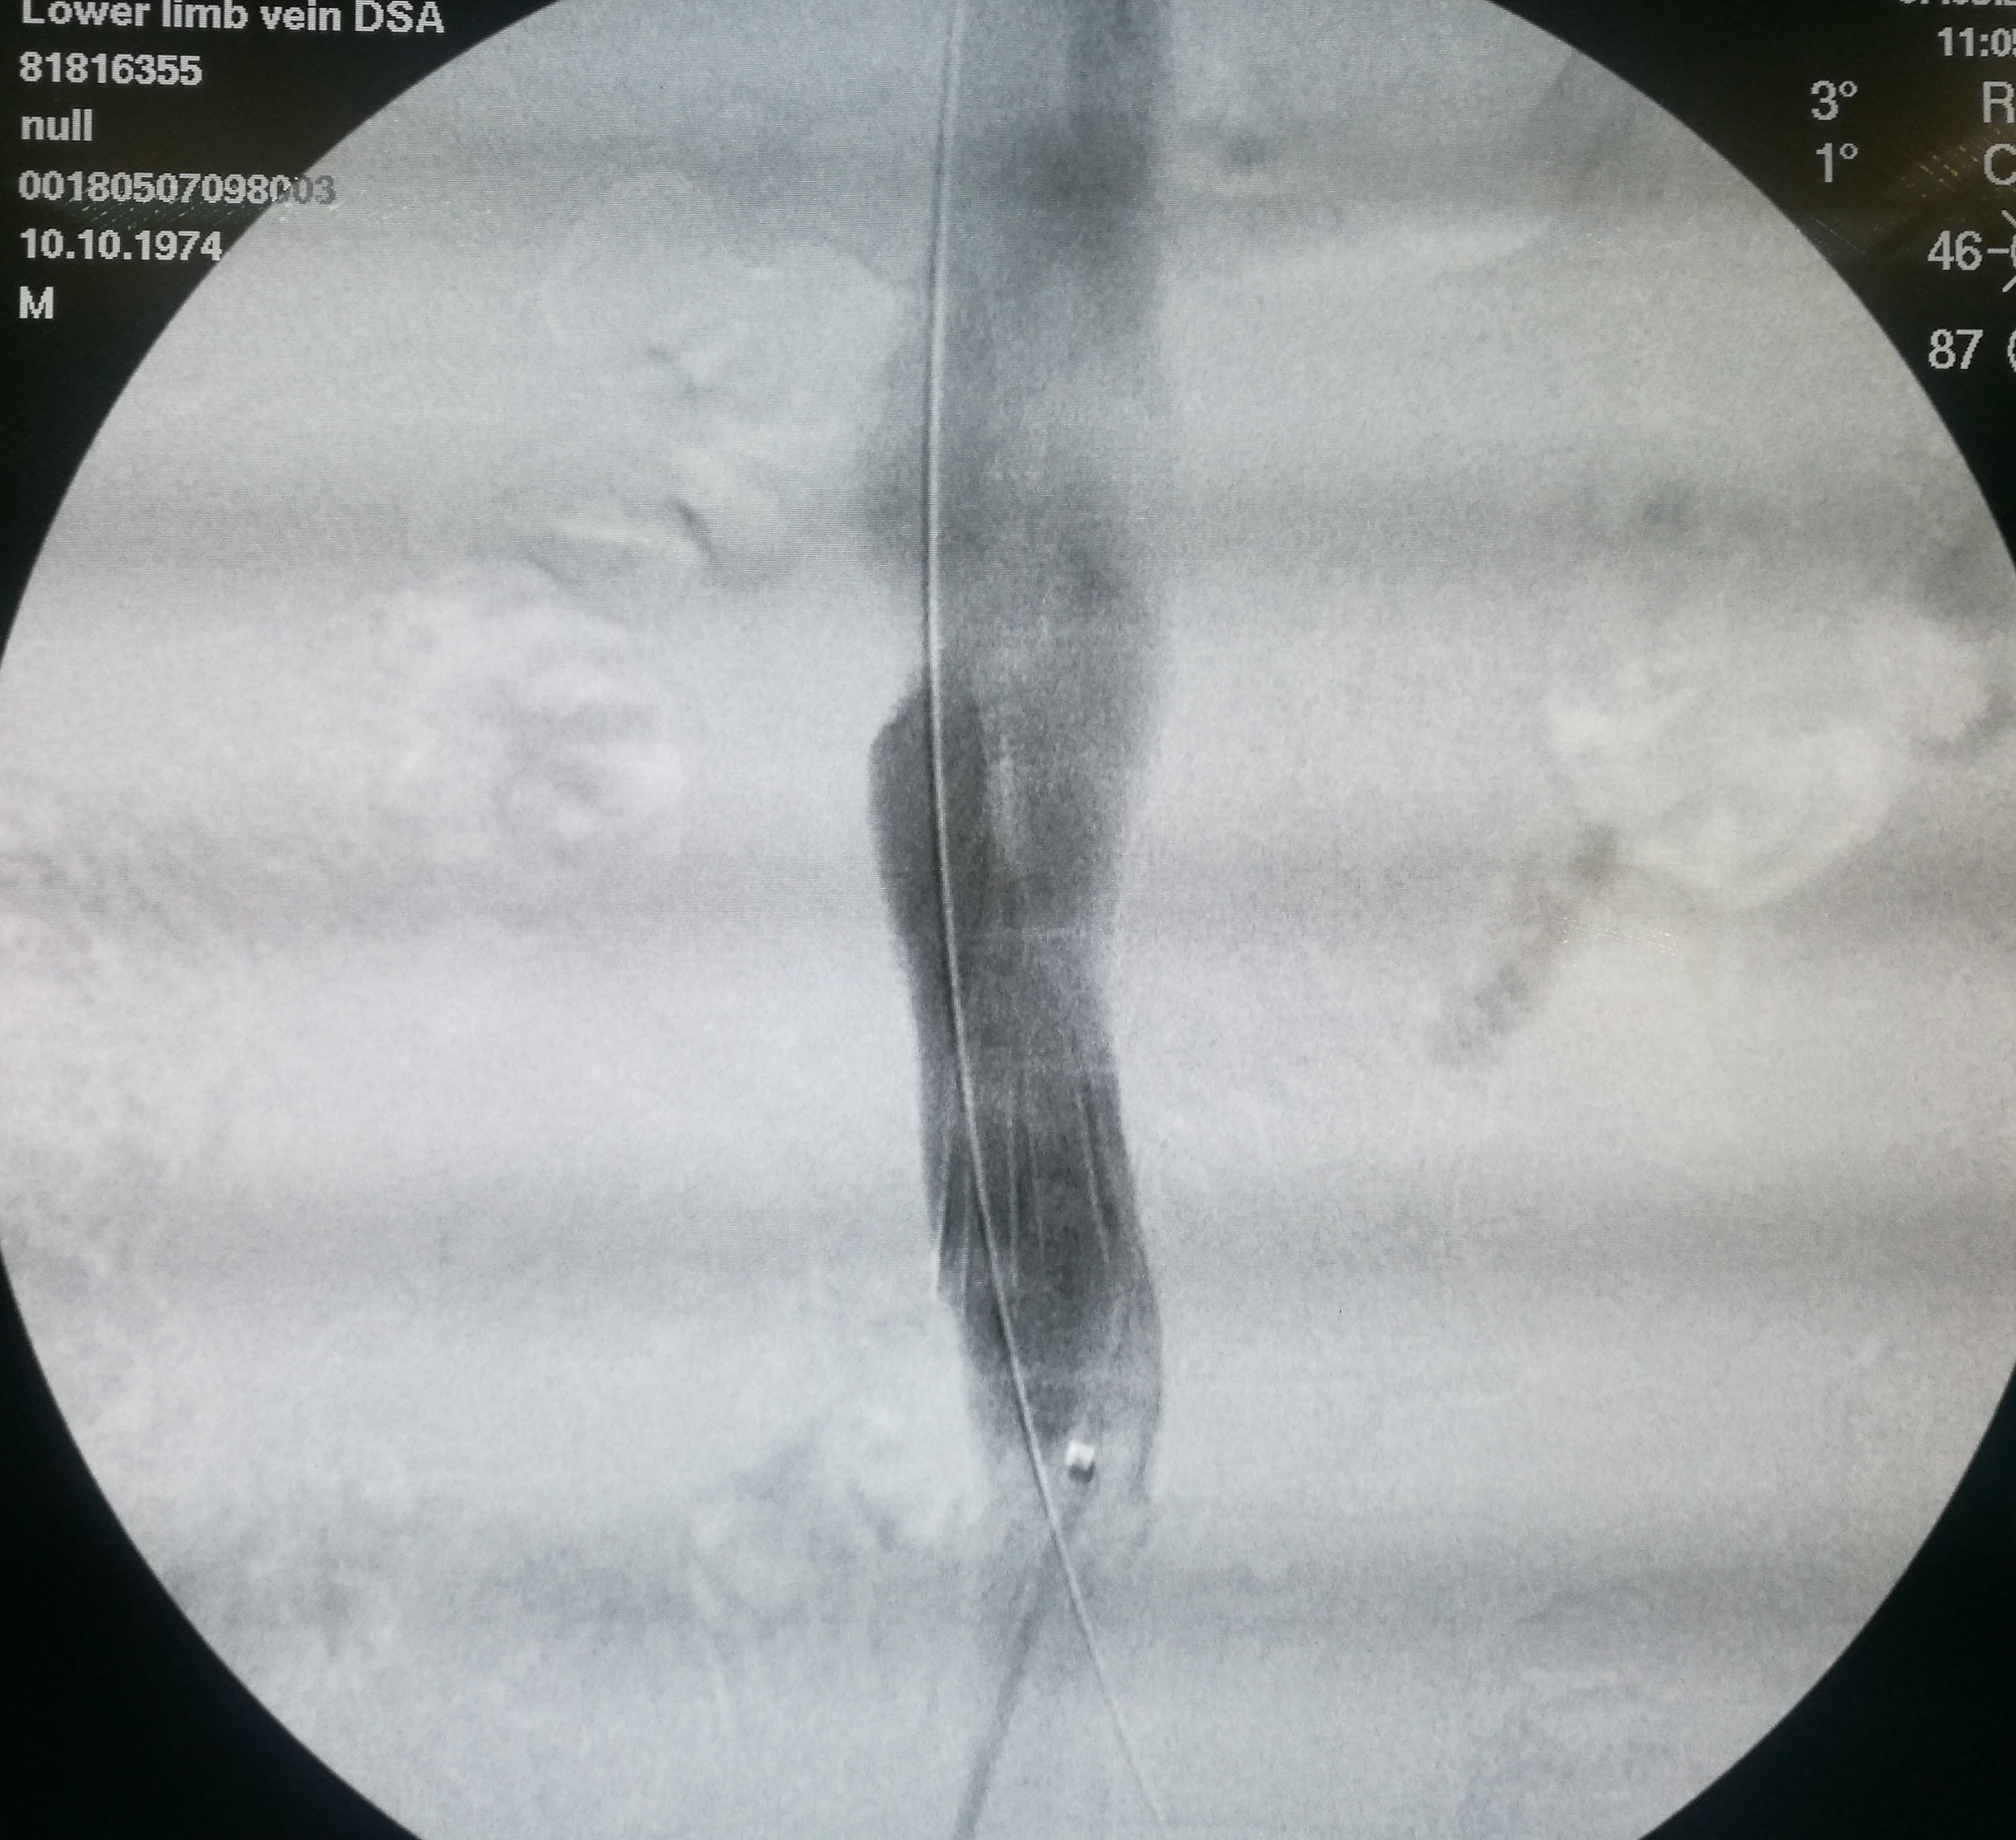

第三个患者是昨天做的,也是反复左下肢深静脉血栓,最近又发作。本次在超声引导下使用肝穿针穿刺左股静脉(其内充满血栓,盲穿无回血),配合超滑导丝,艰难前行约7-8cm后送入血管鞘,之后用导管导丝配合,进入到中线右侧,但从导丝头端的活动度看,未能回到下腔静脉。穿刺右侧股静脉,用SIM1导管从下腔静脉内逆行钩选左侧髂总静脉,在髂总远侧实现和左侧导管的对接,建立真腔轨道。之后在下腔静脉内植入滤器,再对左侧髂总、髂外静脉进行扩张,植入支架。

左髂静脉血栓闭塞

左侧导丝不能回到下腔静脉管腔内

在下腔静脉内留置滤器

植入的支架